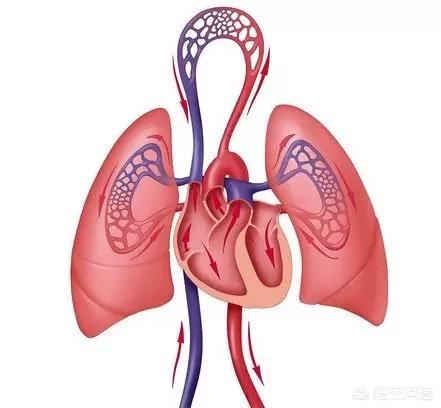

Type III : lésions cardio-pulmonaires

Les personnes souffrant de troubles cardiaques et pulmonaires, de maladies cardiaques et d'emphysème ont tendance à avoir besoin d'une plus grande quantité d'oxygène et à respirer fortement pour ne pas être privées d'oxygène ; elles sont donc également sujettes à la sécheresse buccale !

Contre-mesure : se réveiller tôt, se frotter les mains et respirer profondément.

Dans la paume de la main se trouve le point Laogong, qui est le point principal du méridien du cœur.

En frottant les mains l'une contre l'autre, on peut masser ce point pour stimuler le cœur à travers les méridiens, ce qui excite les organes et aide le corps à récupérer rapidement son énergie physique.

Après s'être réveillé tôt, on peut aller sur le balcon, ouvrir la fenêtre, ou, pour trouver un endroit d'air frais, pratiquer la respiration profonde, on peut expirer l'ancien et réguler la fonction du cœur et des poumons.

Lors de l'inspiration, l'abdomen est légèrement ouvert vers l'extérieur, et lors de l'expiration, l'abdomen est fermé vers l'intérieur, de sorte que le diaphragme, qui contrôle la respiration, s'enfonce, afin d'augmenter la capacité de la cavité thoracique et d'étendre la fonction des poumons, de manière à atteindre l'objectif de l'expiration de l'ancien et du nouveau et à réguler la fonction du cœur et des poumons.